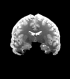

Figure 6: Example field maps (Subject ID 826353) at initialization (top row) and after optimization with Gauss-Newton (bottom row). The first column uses the proposed optimal transport initialization scheme. The middle column uses the same scheme with an additional Gaussian blur to promote smoothness. The right column uses the coarse-to-fine multilevel initialization scheme from HySCO with five levels, and the final field map is optimized at the original image resolution. The multilevel initialized field map is smooth by construction and further optimized to improve the relative image distance at the full resolution. The optimal transport initialization accurately corrects the distortions but is not smooth in the non-distortion dimensions unless blurred with a Gaussian. After the fine-level optimization all field maps are visually similar.